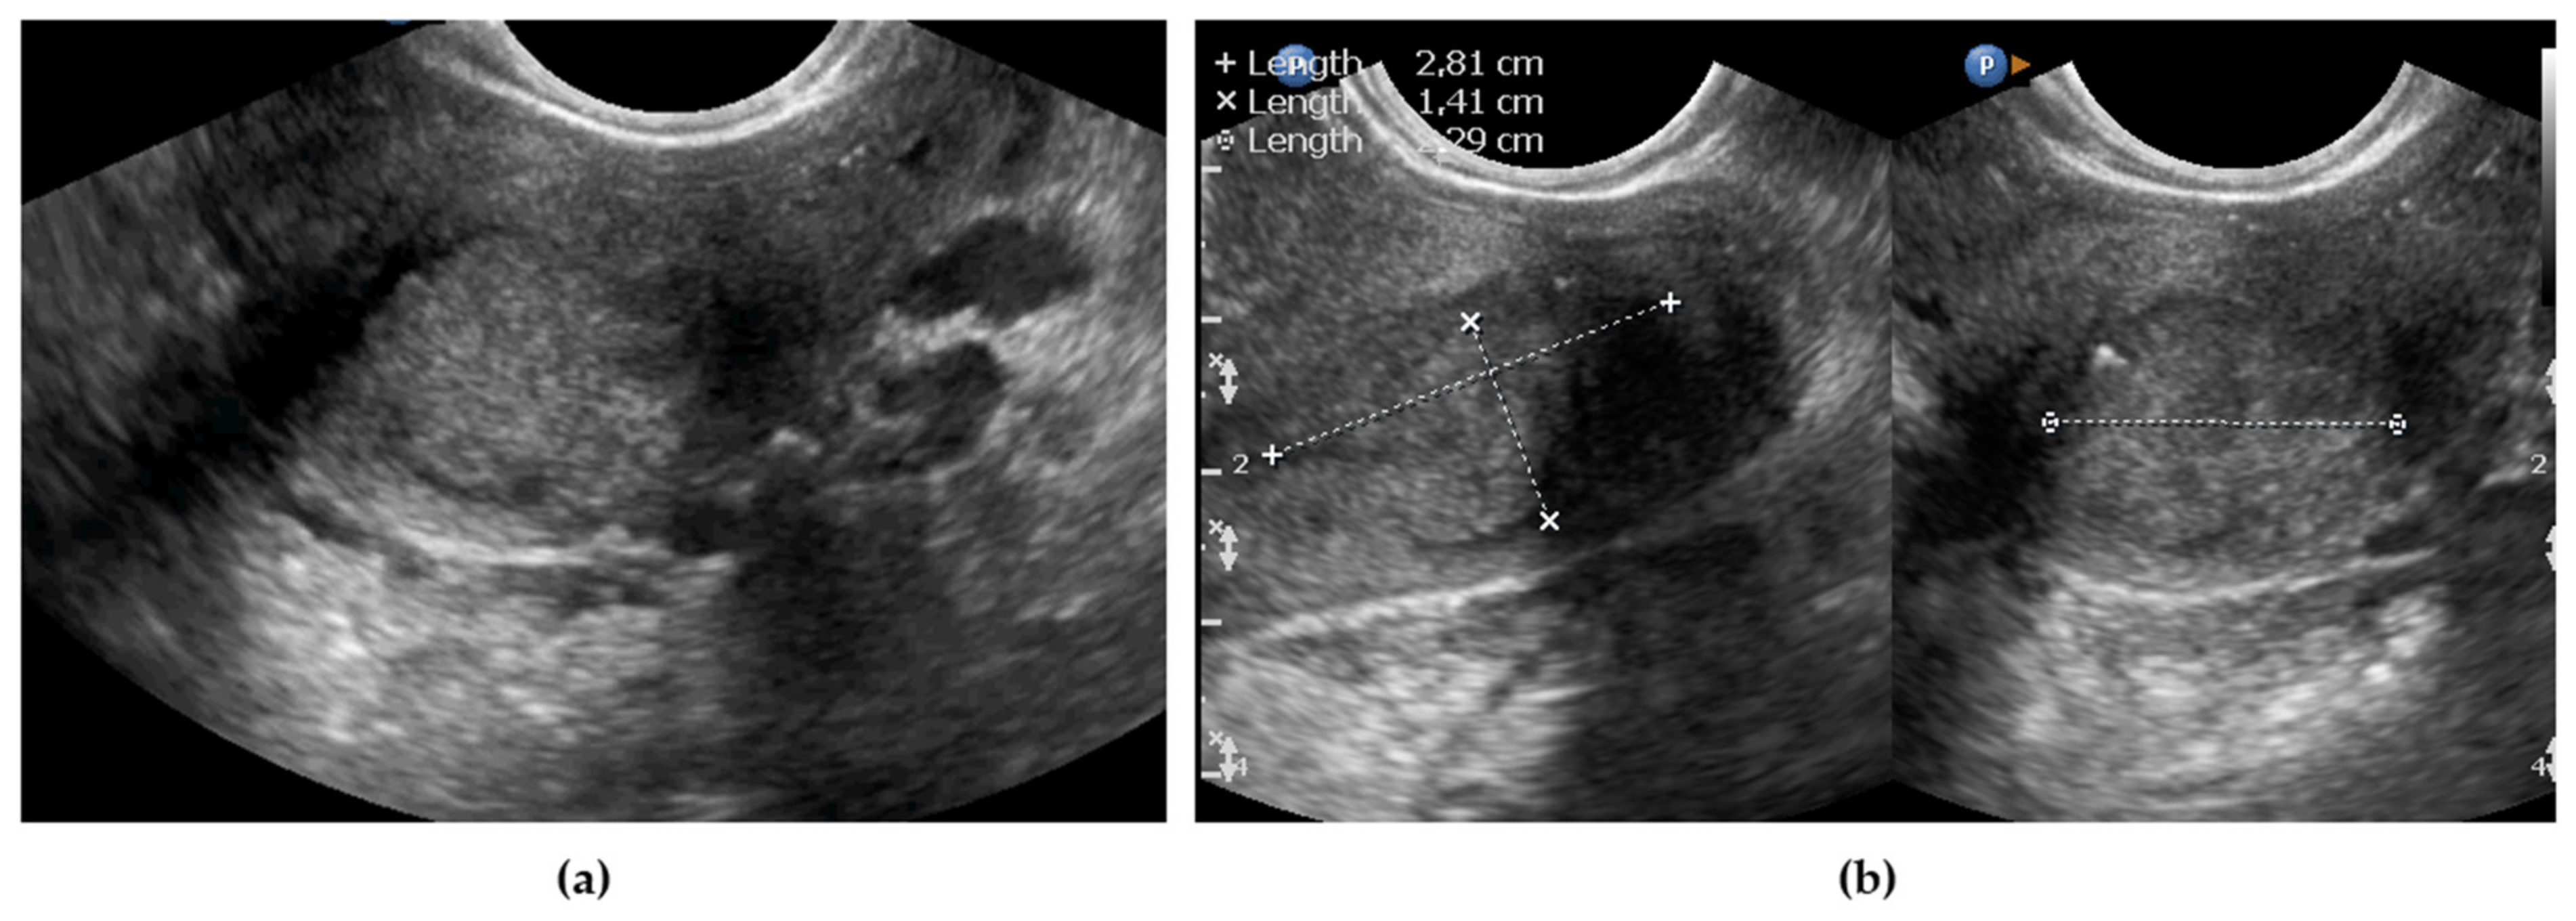

2.3.1. Endovaginal/Transrectal Ultrasonography

3.1. Tumor Detection and Tumor Size